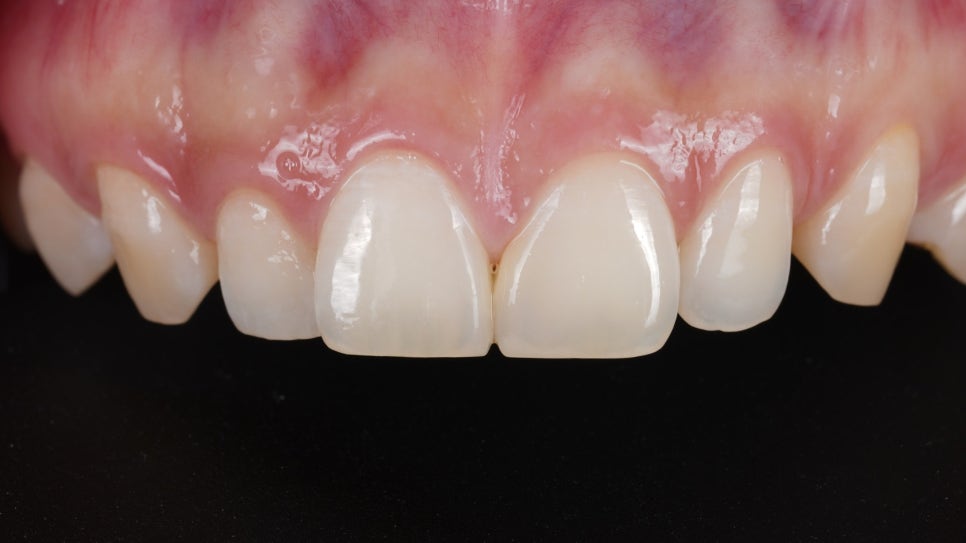

러버댐을 장착하고 Unica Proximal을 사용하여 레진으로 앞니 사이 모양을 디자인하면서 형태를 잡아줬습니다.

마무리로 아주 얇은 연마 기구(soflex)를 활용하여 매끄럽게 다듬어 드렸죠.

촬영일 : 251121

벌어진 사이가 자연스럽게 메워진 것을 볼 수 있었어요.

촬영일 : 251121 / 251121

블랙 트라이앵글을 메울 때 중요한 건 단순히 “틈을 없애는 것”이 아니라 모양이 자연스러운지, 잇몸이 건강하게 차오를 공간이 있는지, 치실이 잘 들어가서 관리가 되는지 이 세 가지를 같이 보는 거라고 생각해요.